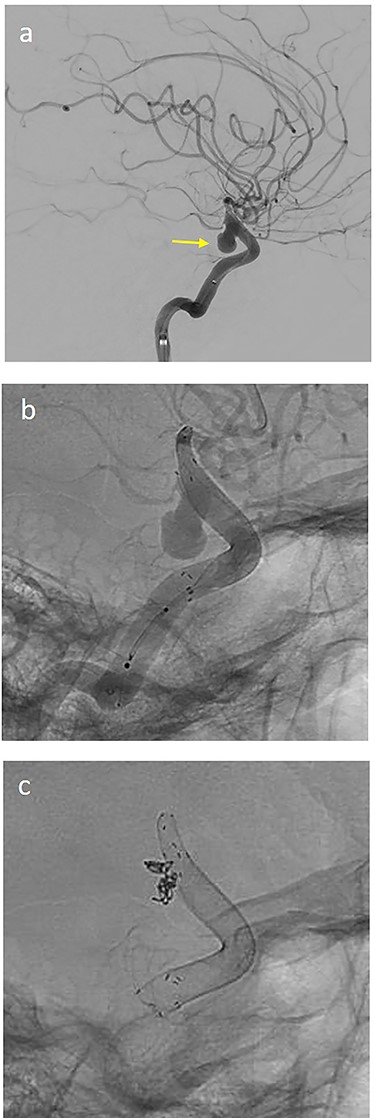

(a) lateral angiogram of left carotid artery showing an ICA aneurysm; (b) 3D reconstruction of the pseudoaneurysm with (c) flow diverter (Derivo®—4,5/20) reconstruction.

On the next day (Day 9 post-op), the patient suffered from acute and devastating headaches, with screaming and enuresis. An emergency computed tomography (CT) was carried out and displayed a prepontine and retroclival subarachnoid hemorrhage (Hunt & Hess Grade I), (Fig. 2). For further evaluation, a digital subtraction angiography (DSA) was conducted, and it showed a pseudoaneurysm of ophthalmic1/supraclinoid2/C23 part of the left ICA, which was directly treated by a flow diverter (Derivo®—4,5/20), with remaining rest flow (Fig. 3). The patient was transferred to the ICU, transcranial doppler sonography was performed and revealed normal flow. In the following course, the patient suffered from Terson’s syndrome and hyponatremia due to SIADH, but after clinical improvement, was transferred back to normal station after 10 days of post-operative monitoring. Furthermore, the patient was plagued with cephalgia and nausea, which could not be compensated with analgetics and antiemetics. On the 20th post-operative day after the epileptic seizure with postictal vigilance reduction, an emergency CTA was conducted showing progressive SAH (Fig. 4) and a growing pseudoaneurysm as well as generalized vasospasm with posthemorrhagic hydrocephalus. For an emergency CSF diversion, an external ventricle drain was placed. The repeated DSA showed a growing false aneurysm which was treated with two additional flow diverters (2× Derivo®—4,5/20) as well as coiling (HydroSoft™ 2/3 and 2× 1,5/2) by endoleak (Fig. 5). The vasospasms were treated by an intraarterial spasmolysis (Fig. 6).